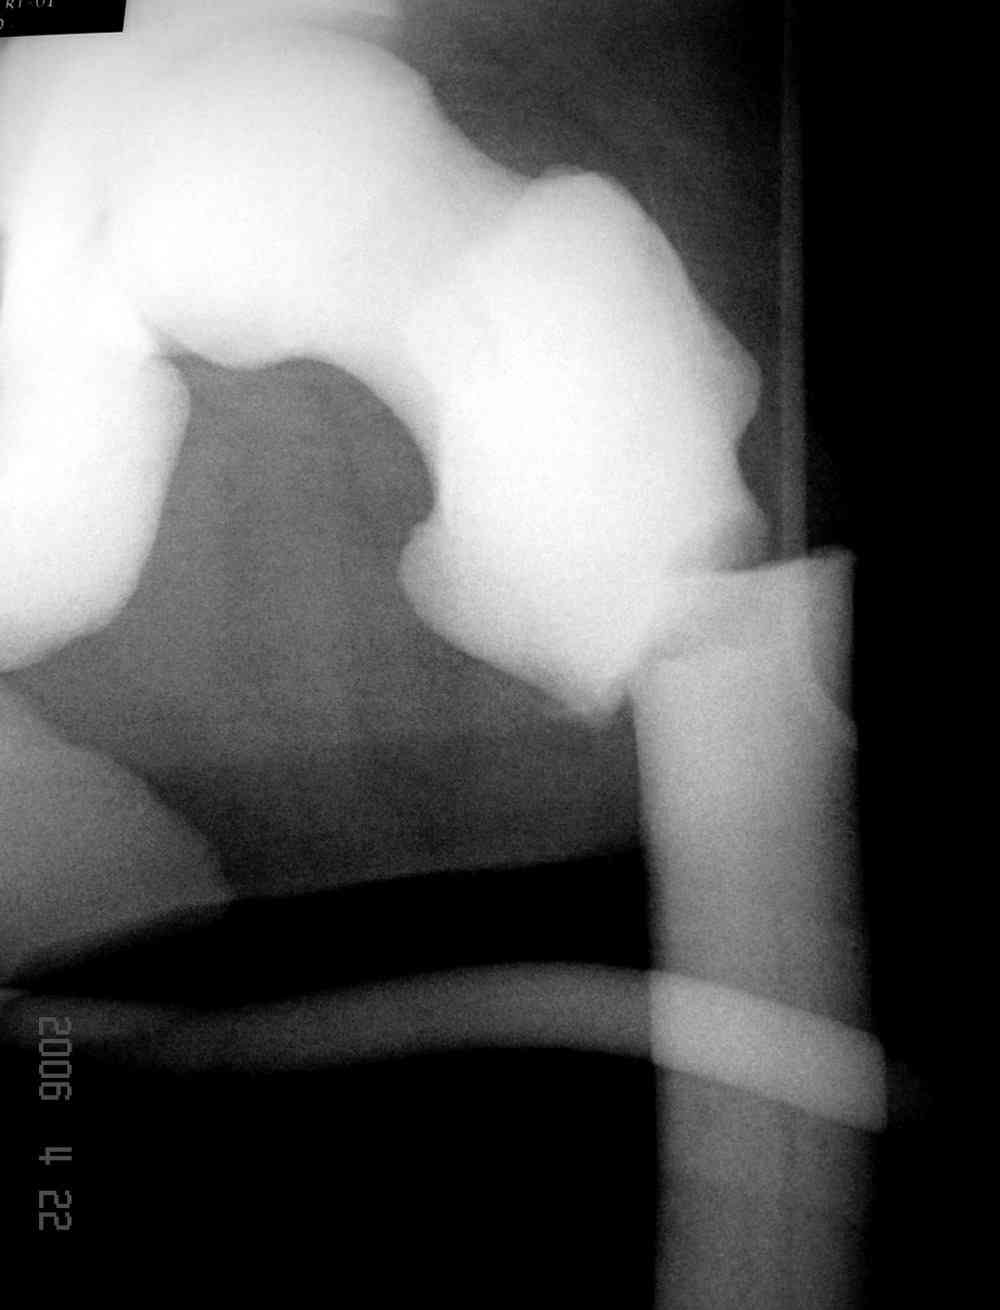

Здесь у меня дополнительные снимки с большим разрешением и в разных режимах, а то те дигитал снимки совсем очень блеклые, может, эти изображени изменят выбор тактики

Не вызывает ли подозрение, что отсутствует медуллярный канал, как просверлить канал?

Канал, возможно, действительно запаян. Но разве большие проблемы его создать и рассверлить (если только это мраморная болезн?) Уверен, в вашей клинике есть для этого всё.